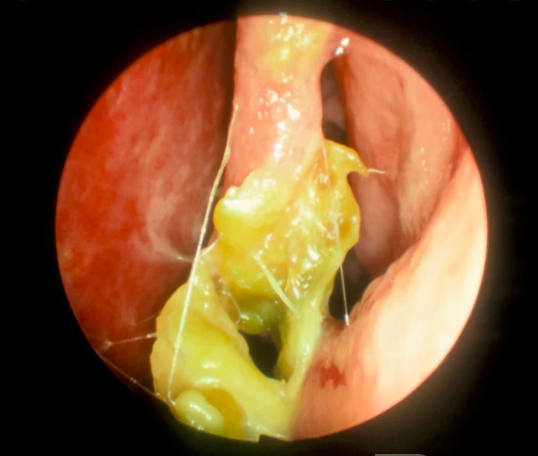

Exemplo de rinite atrófica

Ozena por Klebisella ozenae

(colonização causa necrose)